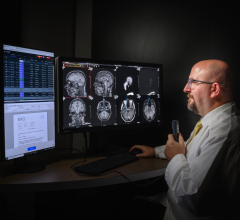

For hospitals and imaging businesses, SeeMyRadiology.com supports streamlined cross-enterprise image communication with other imaging businesses and referring physicians. This streamlined process aims to eliminate the red tape of hardcopy image sharing and the time-consuming and cumbersome production of CDs. The application integrates with any PACS and represents a major step towards the comprehensive electronic medical record (EMR), according to the company.

According to SeeMyRadiology.com pilot user, Phil Larkin, PACS operations manager for Ohio State University Medical Center, “We have already documented that SeeMyRadiology.com and its instant electronic image sharing played a key role in saving the lives of six patients. Without SeeMyRadiology.com, our clinicians would not have had access to critical medical images to make the appropriate clinical decisions. By gaining timely access to these images, we were able to significantly impact outcomes.”